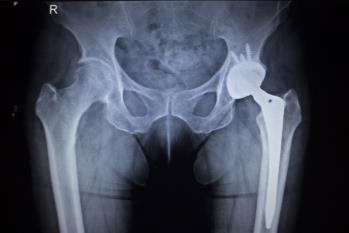

HIP REPLACEMENT SURGERY